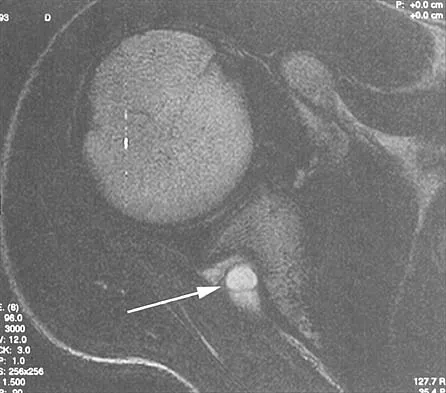

A coronal MRI scan through the shoulder joint is shown in Figure 26. The cyst indicated by the arrow will most likely cause compression of what nerve?

Explanation

The MRI scan shows a ganglion cyst in the region of the spinoglenoid notch. These are difficult to diagnose clinically but are readily apparent on MRI. They usually cause compression of the suprascapular nerve and weakness of the infraspinatus and supraspinatus muscles. Resnick D, Kang HS (eds): Internal Derangements of Joints: Emphasis on MR Imaging. Philadelphia, PA, WB Saunders, 1997, pp 306-309.

References:

- Iannotti JP, Ramsey ML: Arthroscopic decompression of a ganglion cyst causing suprascapular nerve compression. Arthroscopy 1996;12:739-745.